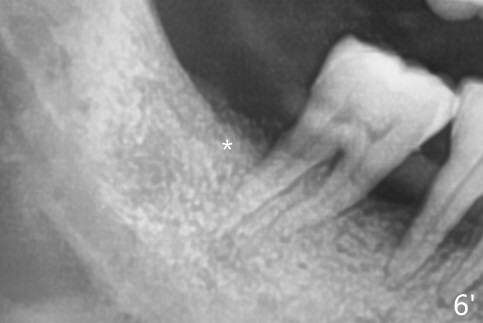

with Severe Bone Loss

A 44-year-old woman (YHM) has generalized moderate localized severe chronic periodontitis (Fig.1). Periodontal abscess develops between the teeth #31 and 32. Since the pain and mobility is more severe at #32 than 31, the former is extracted (Fig.2). After thorough curettage and copious irrigation, Osteogen plug is placed in the distal portion of the socket (Fig.3, 4 O), while allograft in the mesial one (B), with collagen plug on the top (C) before suturing (Fig.5). The tooth #31 is stable and pain-free with formation of new bone distal 7 months postop (Fig.6,6' *), while bone loss at #3 and 4 is more severe.